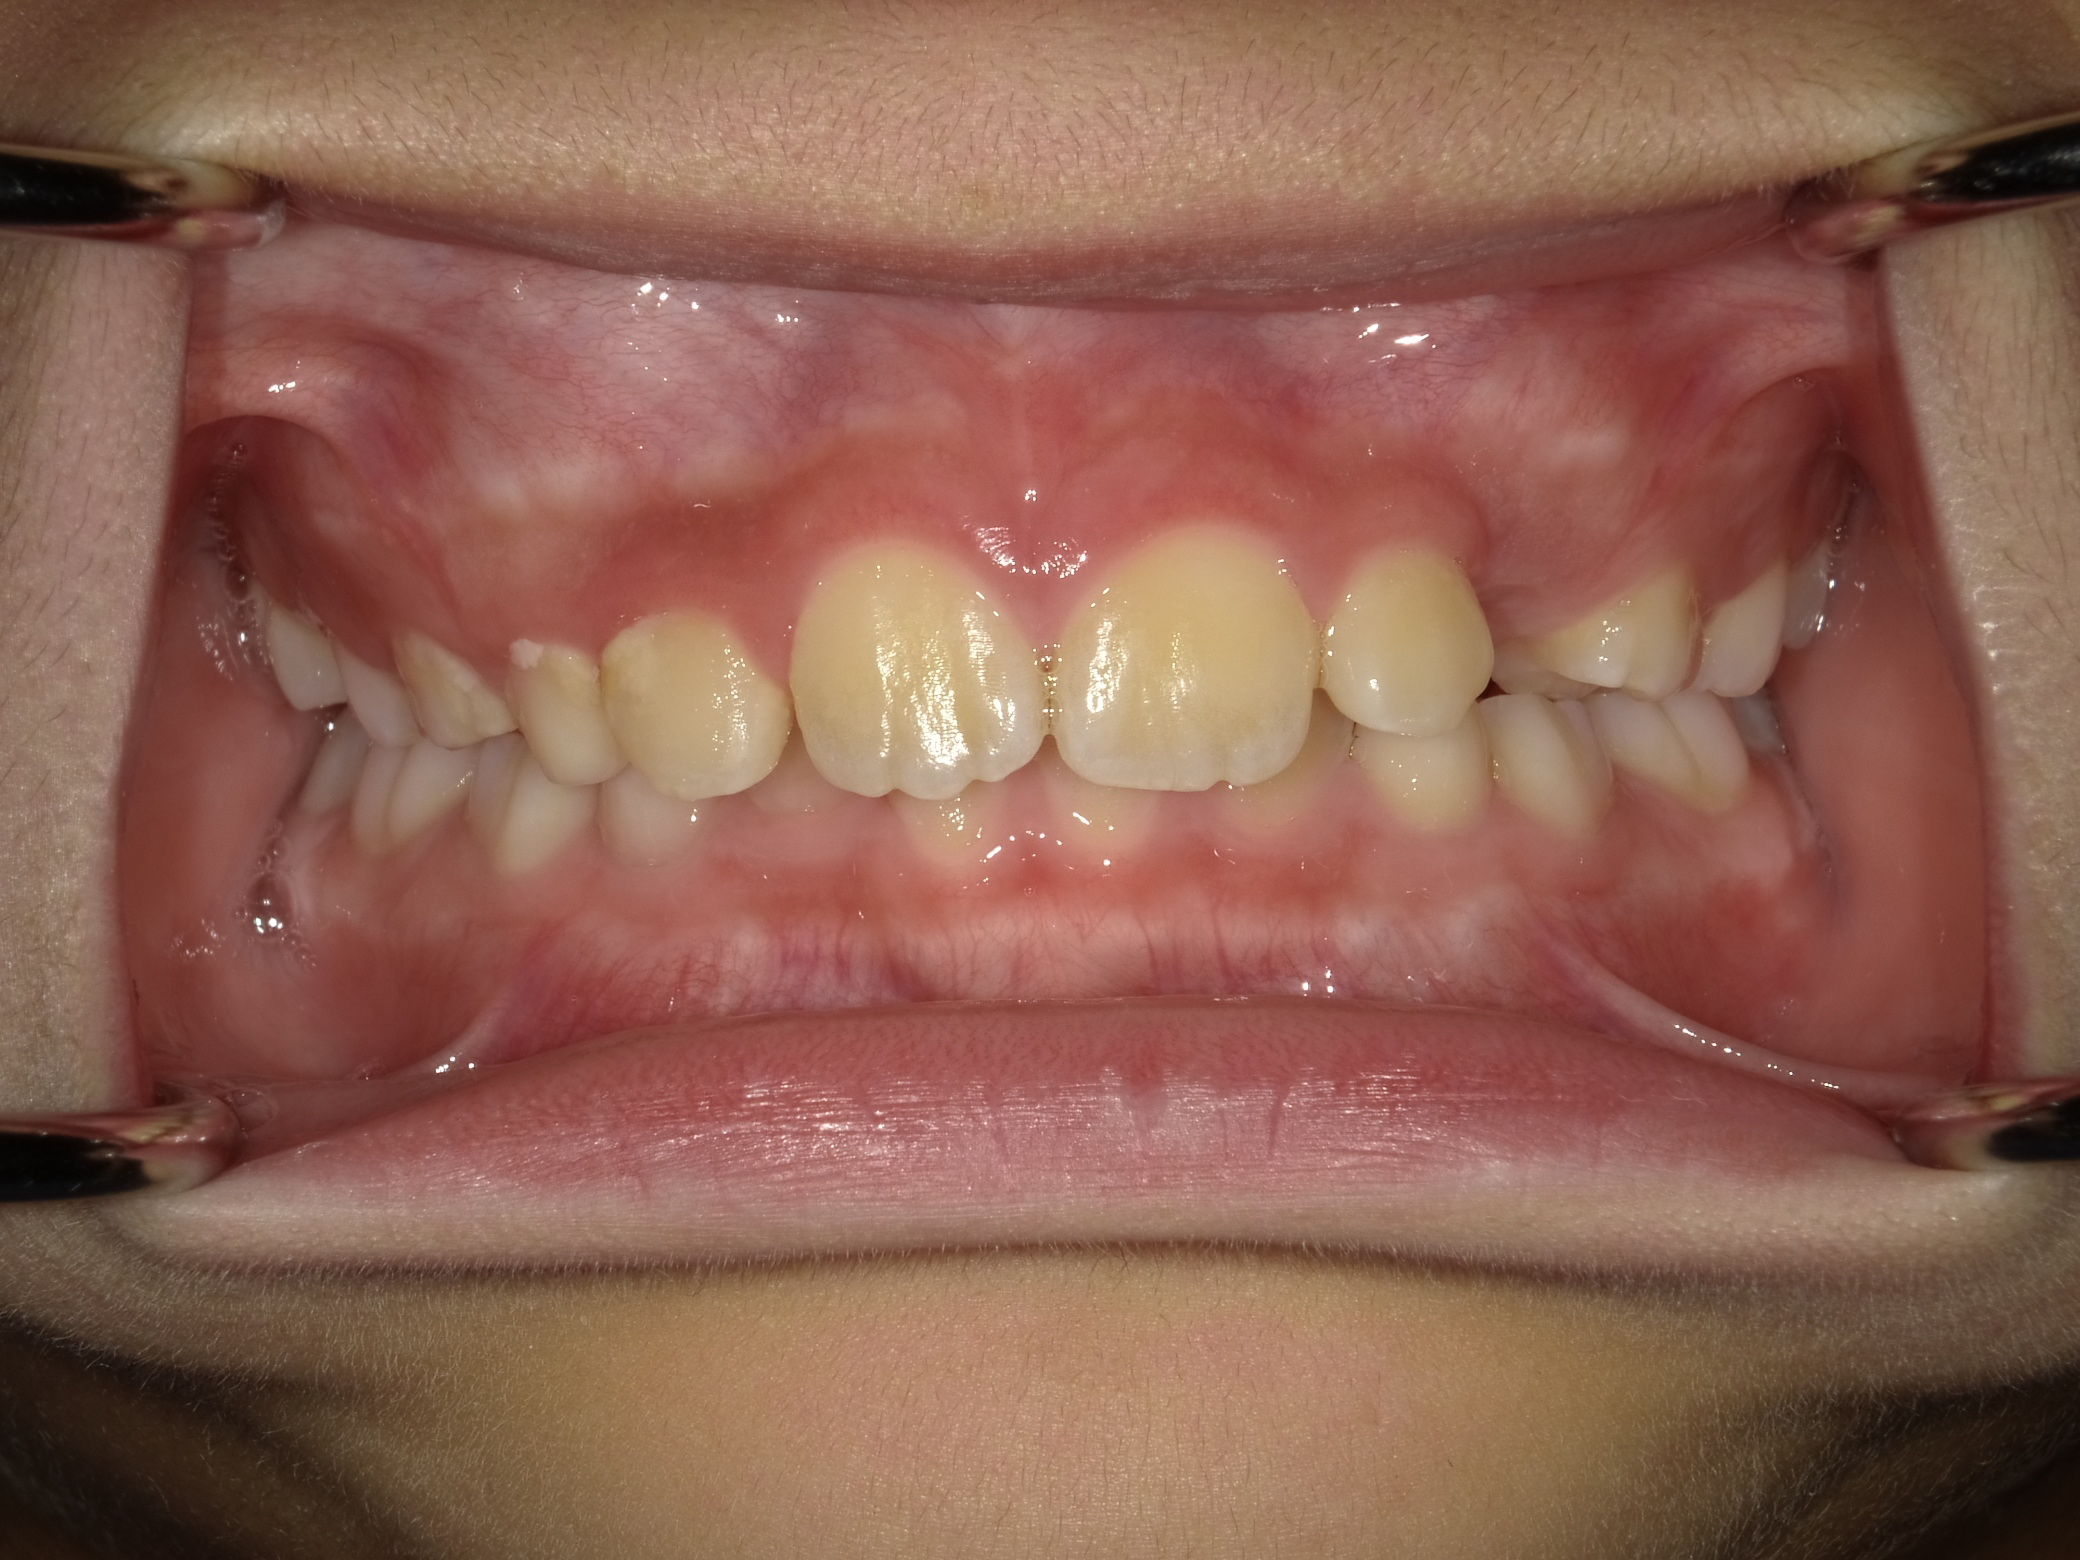

主訴:下の前歯が内側から生えてきた。

治療概要:黄色の丸の部分、まだ乳歯が抜けずに永久歯が内側から生えてきています。このままではこの乳歯は自然と抜ける可能性は低いので、まず、乳歯の抜歯を行いました。

治療前の状態

下の前歯も左右とも内側に生えている歯が並ぶスペースがなく、このままでは凸凹の状態が残ります。

また、横顔を見ても上唇が突出し、上顎前突(いわゆる出っ歯)の状態です。上の歯が下の歯を全て覆い前から見ても下の歯が見えません。

このままでは、将来的に奥歯の負担が大きくなり、歯を失う原因になる可能性があります。叢生(凸凹)の改善と、上顎前突の改善を目的に1期矯正を開始しました。